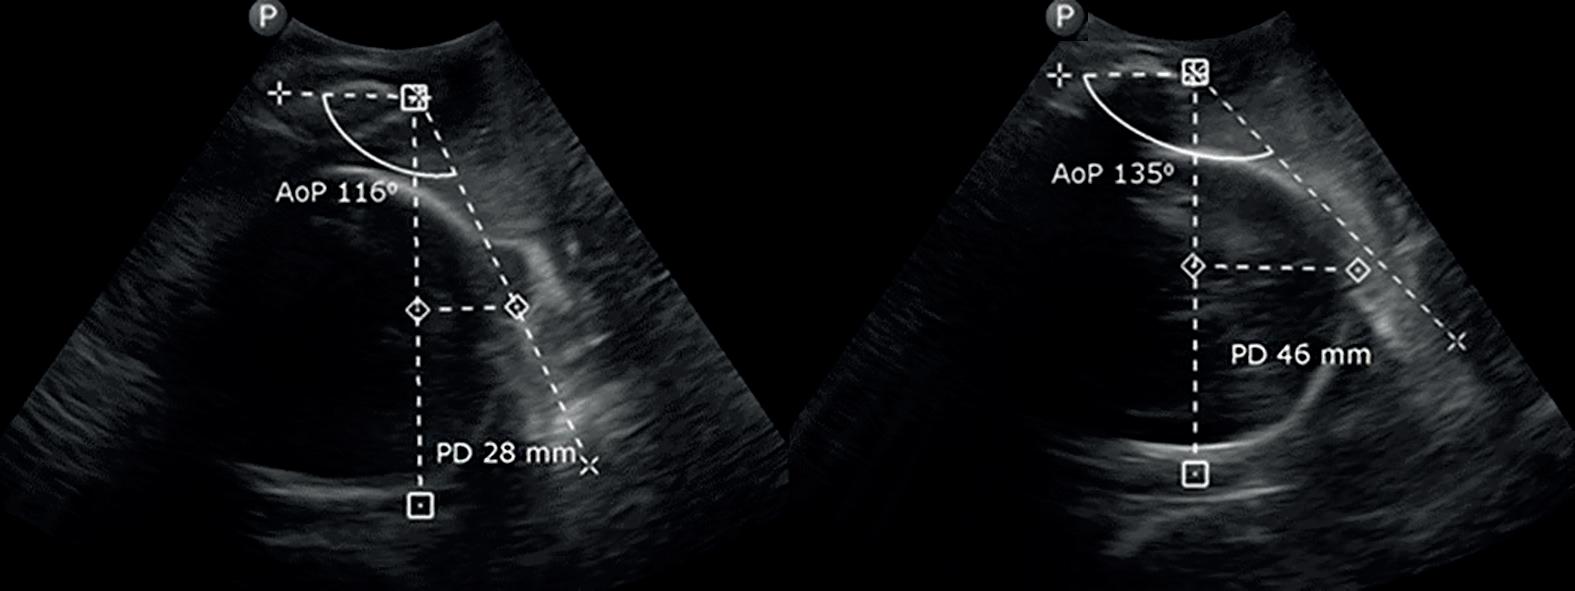

The Positive Effect of Water Immersion on Labor Progress Assessed by Intrapartum Ultrasound Examination

Pozytywny wpływ zastosowania immersji wodnej na postęp porodu oceniany metodą ultrasonografii śródporodowej